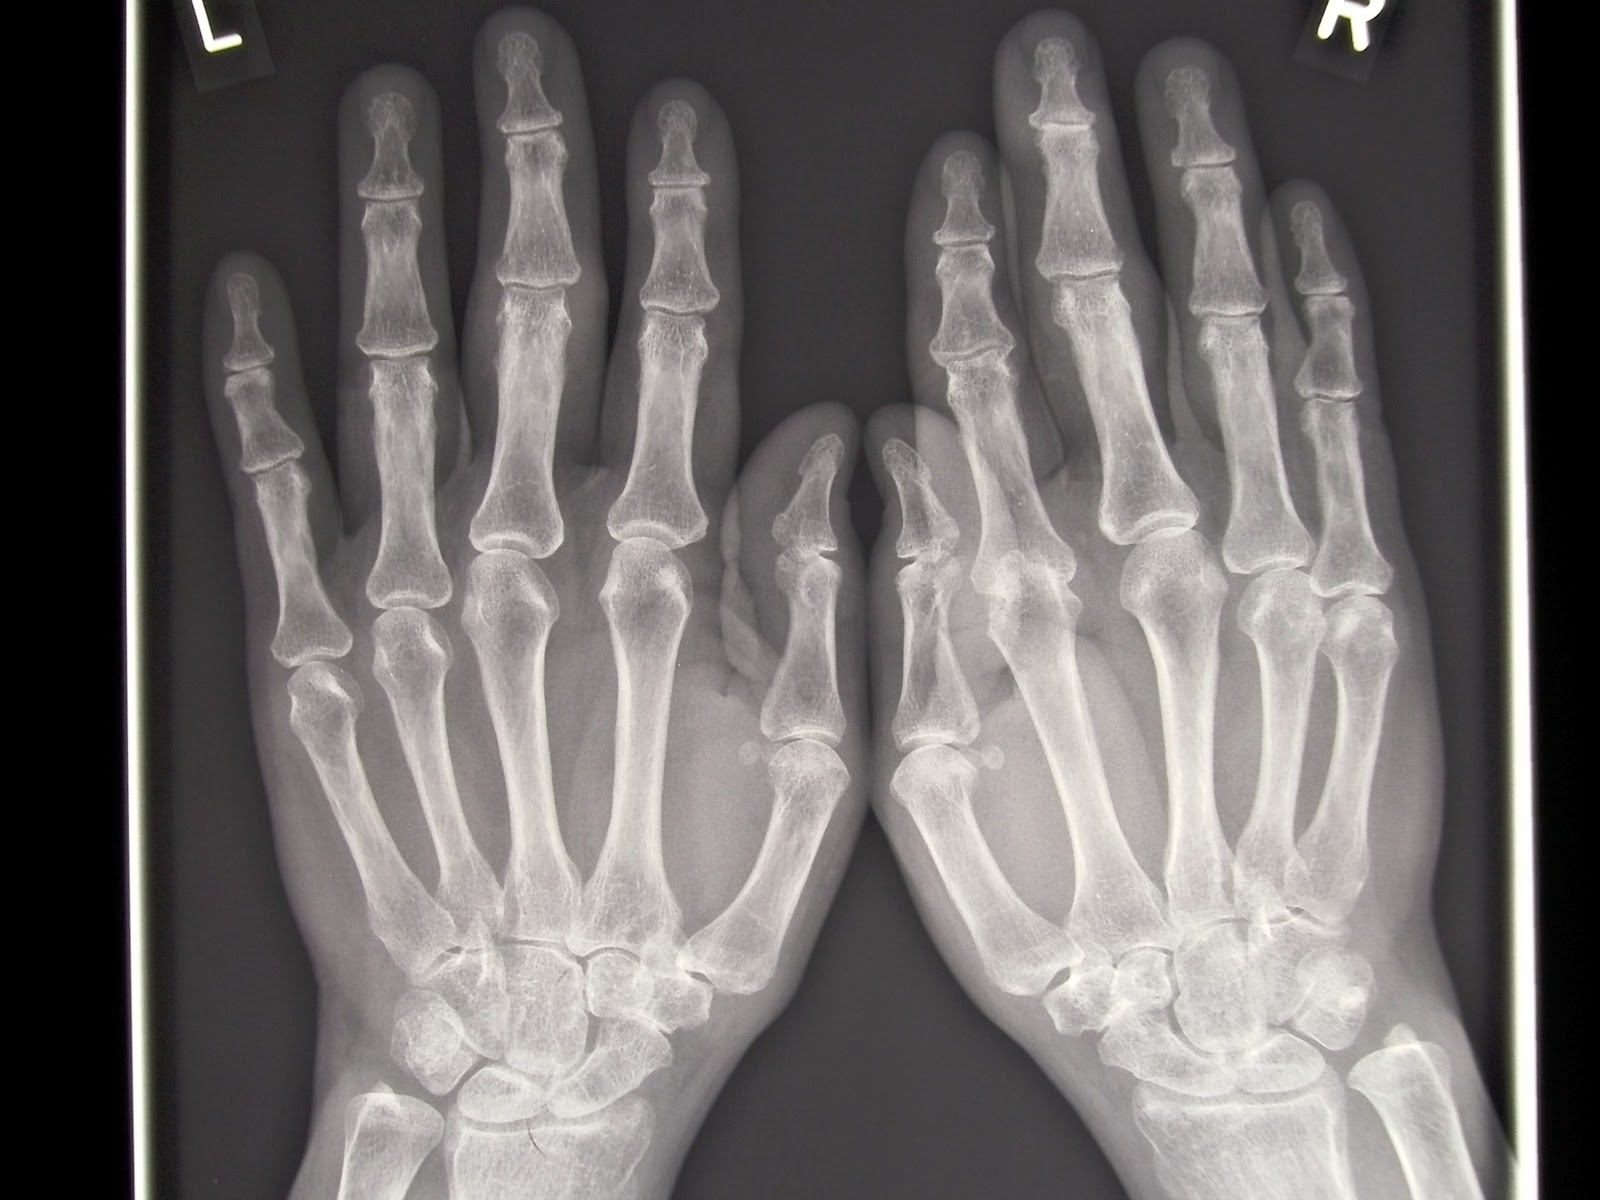

Rheumatoid Arthritis Hands X Ray Chest X Ray Findings In Rheumatoid Arthritis Web chest radiographs serve as a good initial screening tool for assessment of emergent and urgent thoracic conditions,. Web diagnosis is based on a combination of clinical, radiographic, and serological criteria. Web radiologists interpreting the chest radiographs of rheumatoid arthritis (ra) patients should report abnormalities. Web thoracic manifestations of ra. When evaluated via chest hrct, pulmonary involvement is evident in. Chest X Ray Findings In Rheumatoid Arthritis.

Rheumatoid arthritis hands Radiology at St. Vincent's University Chest X Ray Findings In Rheumatoid Arthritis Web chest radiographs serve as a good initial screening tool for assessment of emergent and urgent thoracic conditions,. When evaluated via chest hrct, pulmonary involvement is evident in a high percentage of ra patients, even in. Web diagnosis is based on a combination of clinical, radiographic, and serological criteria. Web radiologists interpreting the chest radiographs of rheumatoid arthritis (ra) patients. Chest X Ray Findings In Rheumatoid Arthritis.